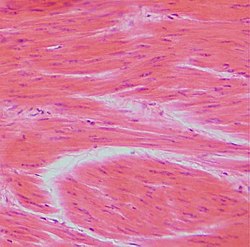

In der Histologie werden Gewebeproben untersucht. Dazu werden mikrometerdünne, gefärbte Gewebsschnitte hergestellt und am Lichtmikroskop beurteilt. Die elektronenmikroskopische Untersuchung von wesentlich dünneren Schnitten (0,01–0,5 µm) fällt vorwiegend in den Forschungsbereich.

Die Verarbeitung von Formaldehyd-fixiertem, Paraffin-eingebettetem Gewebe inklusive der Hämatoxylin-Eosin-Färbung stellt die weltweite Routine-Methode der Pathologie dar und dauert durchschnittlich ein bis zwei Tage von der Probenannahme bis zur Befundung. Im Gegensatz zum klinisch-chemischen Labor sind viele Arbeitsschritte von Hand durchzuführen. Besonders die Schnittherstellung am Mikrotom bedarf großen Geschicks.

Es gibt eine Unzahl verschiedener histologischer Färbungen, die im Laufe der letzten 120 Jahre entwickelt wurden. Der Großteil stammt aus den ersten 30 Jahren des vorigen Jahrhunderts. Im modernen Histolabor hat sich eine überschaubare Anzahl an Färbungen durchgesetzt. An erster Stelle steht die Hämatoxylin-Eosin-Färbung (HE-Färbung) als Routine- und Übersichtsfärbung. Dafür werden meist computergesteuerte Färbeautomaten eingesetzt. Daneben werden für bestimmte Fragestellungen sogenannte Spezialfärbungen (meist von Hand) durchgeführt.